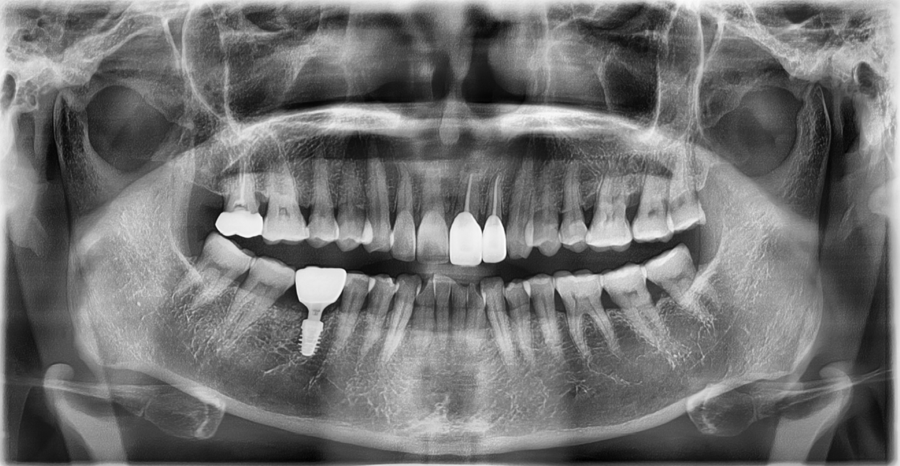

임플란트 고정 상태 자체는 비교적 안정적이었지만,

• 교합 시 힘이 전달되는 방향

• 보철물과 주변 치아의 맞물림

• 씹을 때 반복적으로 자극이 가해지는 지점

이 복합적으로 작용해

시림과 불편감이 나타나고 있었습니다.

임플란트는 심어져 있는 구조물보다

실제로 사용되는 환경이 더 중요한 치료라는 점을

확인할 수 있던 케이스였습니다.